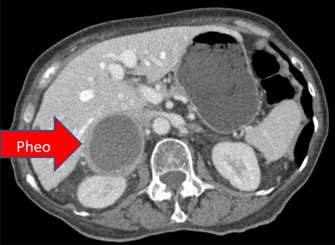

R. pheo, Liver >

Larger image >